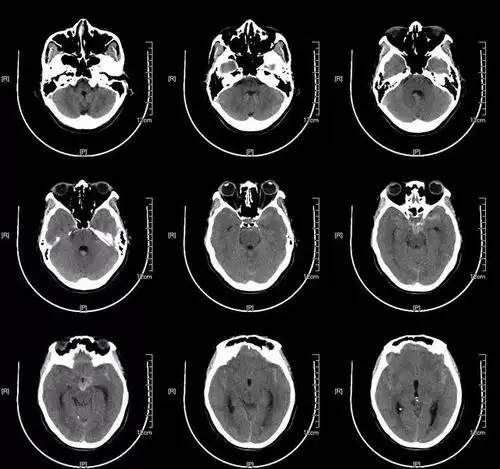

67超急性期大面积脑梗死ct平扫表现

患者入院后头颅ct提示蛛网膜下腔出血,以脑干前方为主,提示后循环

头部ct影像解剖

颅脑ct怎么看正常和异常影像分别是什么